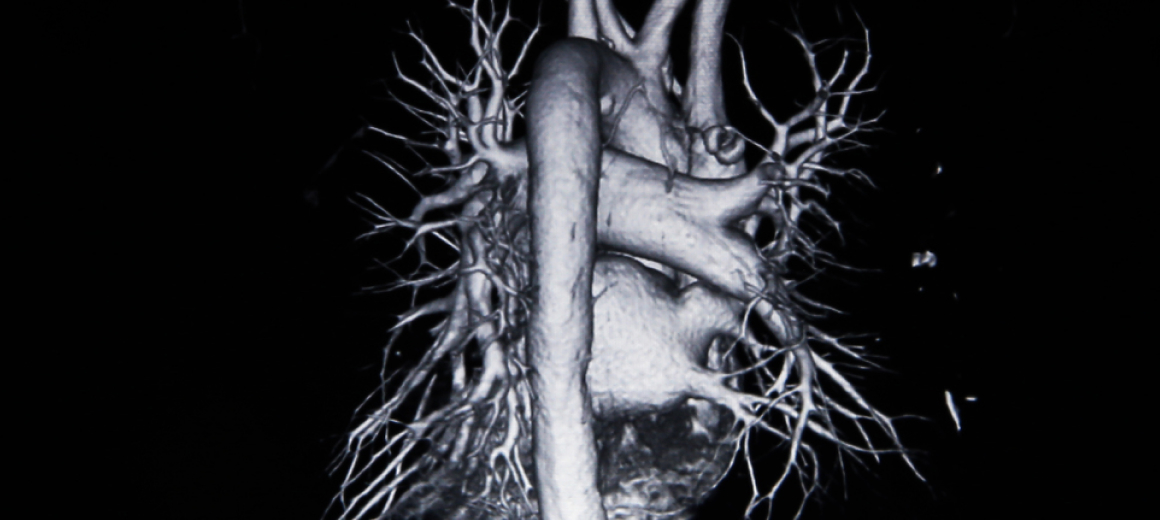

MRI検査 Magnetic Resonance Imaging

おもに、脳腫瘍、脳梗塞などの発見に役立ちます。頭蓋骨の影響を受けずに脳内を診断することができ、全方位的に、脳腫瘍、脳梗塞などの病変の場所、形や広がりを特定できます。